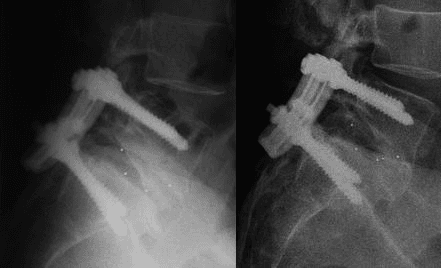

PLIF an invasive spinal fusion surgery used to stabilize the spine and relieve pressure on spinal nerves. The term "posterior" refers to the surgical approach—the surgeon accesses the spine from the back. "Lumbar" indicates the lower back region where the procedure is performed. "Interbody Fusion" describes the main part of the surgery: removing a damaged intervertebral disc and fusing two or more vertebrae using a bone graft or implant.

- Implant Misplacement: The screws, rods, and cages used to stabilize the spine must be placed with precision. If a screw is misplaced, it can irritate a nerve or fail to provide adequate support, potentially requiring another surgery to correct it.